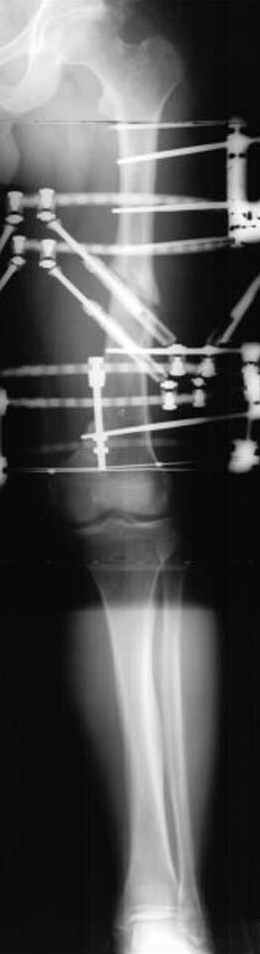

Несколько снимков из моей коллекции, чтобы разьяснить, почему мы до сих пор делаем различные варианты остеотомии.

На рисунке N1 предоперационный план лечения ложного сустава шейки бедра- линия ложного сустава, угол и направление введения импланта, клиновидная остеотомия в градусах и миллиметрах, второй снимок после коррекции, расчет, на сколько удлиняется конечность и размеры импланта;

N3 рисунок окончательный снимок, после операции моя рентгенограмма должен выглядеть примерно как эта картина. На N4 снимке клин перед удалением; N5 послеоперации 3 нед.; N6 окончательная рентгенограмма.

(доложен в Ст. Петербурге 2003 и в Москве 2004)

варус при проксимальном отделе 95 градусной пластиной.

Отправитель: Djoldas Kuldjanov 23 Ноябрь 2004, 18:21

пластическая модель; и коррекция бедра аппаратом Илизарова.